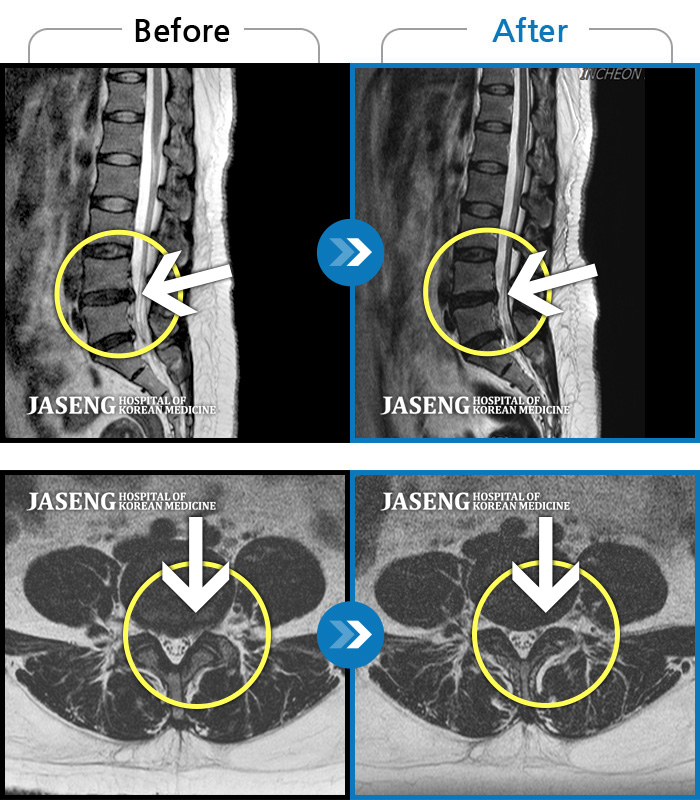

ȯںп Ǹ ǿ ԿǾ, ο ġ ۿ Ƿ ġḦ Ͻñ ٶϴ.